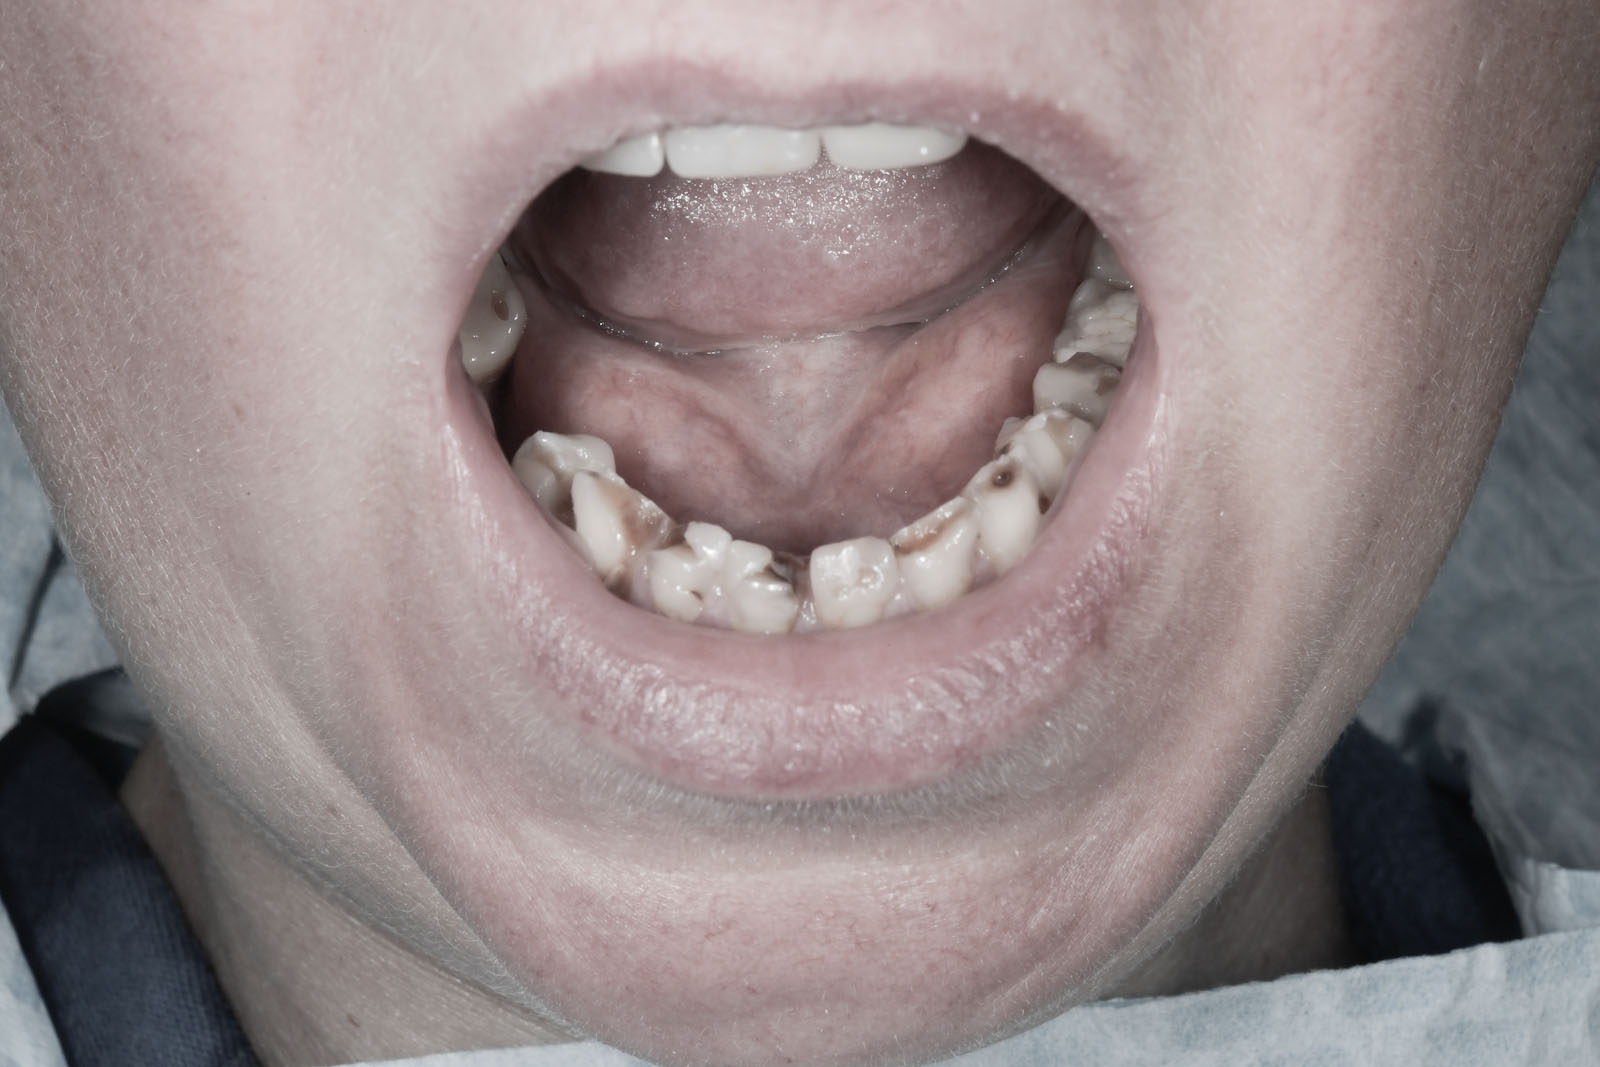

Protetyka stomatologiczna to dział stomatologii zajmujący się odtwarzaniem pierwotnych warunków zgryzowych po całkowitej lub częściowej utracie zębów albo po ich uszkodzeniu. Pokrewną dyscypliną jest protetyka szczękowo-twarzowa, której zadaniem jest rekonstrukcja utraconych tkanek oraz narządów zlokalizowanych w obrębie twarzoczaszki i jamy ustnej.

Przywracanie funkcji jamy ustnej polega na wykonywaniu uzupełnień protetycznych utraconych zębów oraz części jamy ustnej. Istnieją dwa typy uzupełnień protetycznych: stałe i ruchome. Różni je od siebie sposób ich utrzymania w jamie ustnej.

Utratę każdego zęba należy uzupełnić możliwie jak najszybciej, ponieważ nawet pojedyncze braki zębowe mogą prowadzić do niekorzystnych następstw dla całego układu żucia. Po utracie zęba dochodzi do zaniku kości wyrostka zębodołowego w wyniku braku jej osiowego obciążenia siłami żucia. Dochodzi do przemieszczania się zębów pozostałych w sąsiedztwo powstałej luki. Mogą się one przechylać, obracać i wysuwać z zębodołu bez względu na to, czy dotyczy to łuku górnego czy dolnego. Ruchy zębowe uzasadnia ich fizjologiczne dążenie do kontaktu ze sobą. Stąd braki zębowe w przeciwstawnym łuku deformują zgryz. Proces ten opisywany jest jako objaw Godona.

W rezultacie prowadzi to do utraty kolejnych zębów. Następstwa postępujących braków zębowych prowadzą do powstania zaburzeń funkcji stawów skroniowo-żuchwowych. Mogą objawiać się trudnościami w rozwieraniu szczęk, bólami mięśni twarzy i głowy w okolicach skroni, jak również prowadzić do zaburzeń trawiennych. Poza funkcją istotna jest również estetyka. Widoczne w uśmiechu braki zębowe, skrócenie dolnego odcinka twarzy, zapadnięcie się warg czy tworzenie się zmarszczek w okolicy ust to tylko niektóre z następstw towarzyszących ubytkom uzębienia. Uzupełnianie braków zębowych przywraca podstawy fizjologii jamy ustnej, ponieważ zęby jako zespół funkcjonują prawidłowo tylko w komplecie.